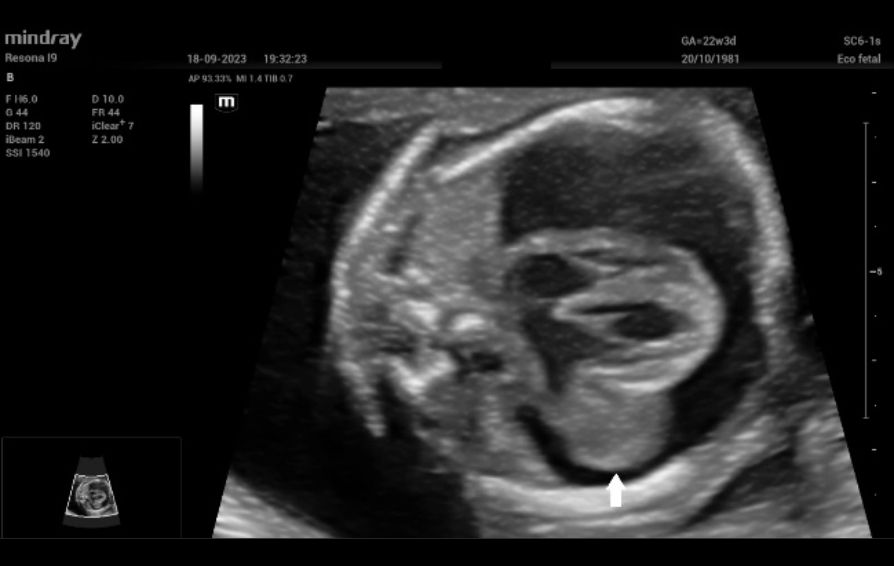

Additionally, a wide muscular ventricular septal defect (VSD) (Fig 2). and agenesis of the ductus venosus with extrahepatic drainage to the inferior vena cava (Fig 3). were diagnosed.

Figure 2: Septal four-chamber view of the fetal heart on dual 2D and Color Doppler imaging. A wide ventricular septal defect (white arrow) is clearly seen.